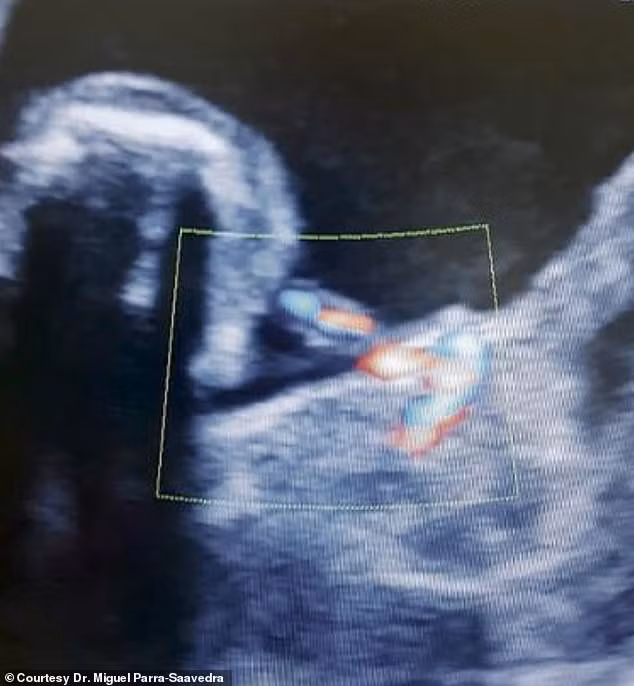

Nhưng trường hợp của bé Itzamara lại vô cùng đặc biệt bởi bác sĩ sản khoa của mẹ bé, Tiến sĩ Miguel Parra-Saavedra, đã phát hiện khối nang trên ảnh siêu âm 3D/4D ở tuần thai thứ 35 của người mẹ.

Bức ảnh siêu âm ở tuần thứ 35 cho thấy một thai nhi khác đang phát triển trong bụng bé Itzamara.

Khi sử dụng máy siêu âm màu với chức năng hiển thị hình ảnh đa màu của mạch máu ở cấp độ cực kỳ chi tiết, Tiến sĩ Parra-Saavedra đã phát hiện một thai nhi bé xíu khác với dây rốn của riêng mình chứ không phải nang gan.